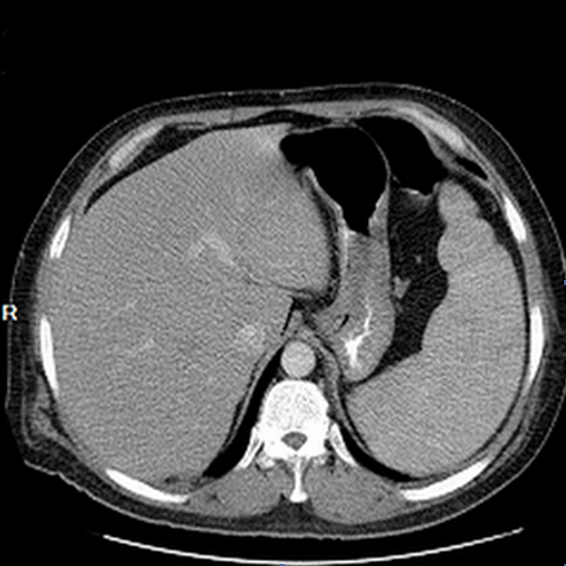

He was lost to follow-up and two months later when he showed up, a 2-cm firm non-tender lymph node was detected in the right axilla. An excisional lymph node biopsy revealed large atypical lymphoma cells located within sub-capsular and para-cortical regions (Figure 3). Immunohistochemistry indicated positive staining for CD20, Bcl-2 and Bcl-6. CD3, CD30, S-100, CD31, CD34 were negative (Figure 4). The diagnosis of DLBCL was established.

Figure 3: Lymph node biopsy showing atypical lymphoma cells located within sub-capsular and para-cortical regions (x200).